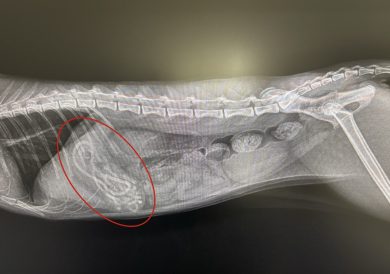

レントゲン検査・エコー検査:レントゲン検査では胃の中にヒモ状の何かがたくさん入っているような像が見られました。エコー検査では胃の中にものが溜まっている所見が得られました。

レントゲン検査やエコー検査からは異物の全体像を把握することが難しく異物が胃の中に留まっているのか、腸の方に一部流れているのかの判断も難しかったので内視鏡での摘出、もしくは胃切開、腸切開での摘出の可能性を考慮し手術を実施しました。